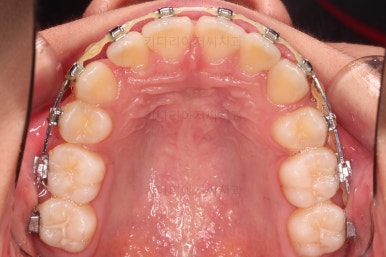

부산치아교정치과 키다리아저씨치과에서 마무리한 입안의 모습입니다.

가지런하게 잘 정렬이 되었고요.

윗니만 발치한 편악발치교정이지만 틈새 없이 공간이 닫혔으며 교합도 잘 맞습니다.

간혹 윗니만 발치를 해서 윗니만 갯수가 적어 교합에 문제가 되지 않나요? 라는 질문을 하시는 경우가 있는데요.

윗니 아랫니는 1:1로 대응 되는게 아니라 지그재그로 서로 엇갈려 있기 때문에 특히 윗니는 하나 모자라도 교합에 전혀 문제 되지 않습니다.

위아랫니가 가지런하게 보기 좋게 배열이 되었고요.

아랫니까지 윗니를 넣음으로써 튀어나와 보이던 앞니의 느낌이 좋아졌습니다.

물론 작은 아래턱에 맞춰 윗니를 뒤로 집어넣어야 해서 자칫 지나치게 들어간 입이 될까 염려되는 조심스러운 케이스였지만, 편악발치를 통해 최소한으로 입을 넣으면서 굉장히 조화롭게 잘 마무리 했습니다.

웃을 때 보이는 앞니의 느낌과 위치가 참 좋아졌네요.

옆 라인도 움푹 들어가 있던 아랫입술 아랫 부분이 완만하게 펼쳐지면서 입매도 많이 좋아졌습니다.